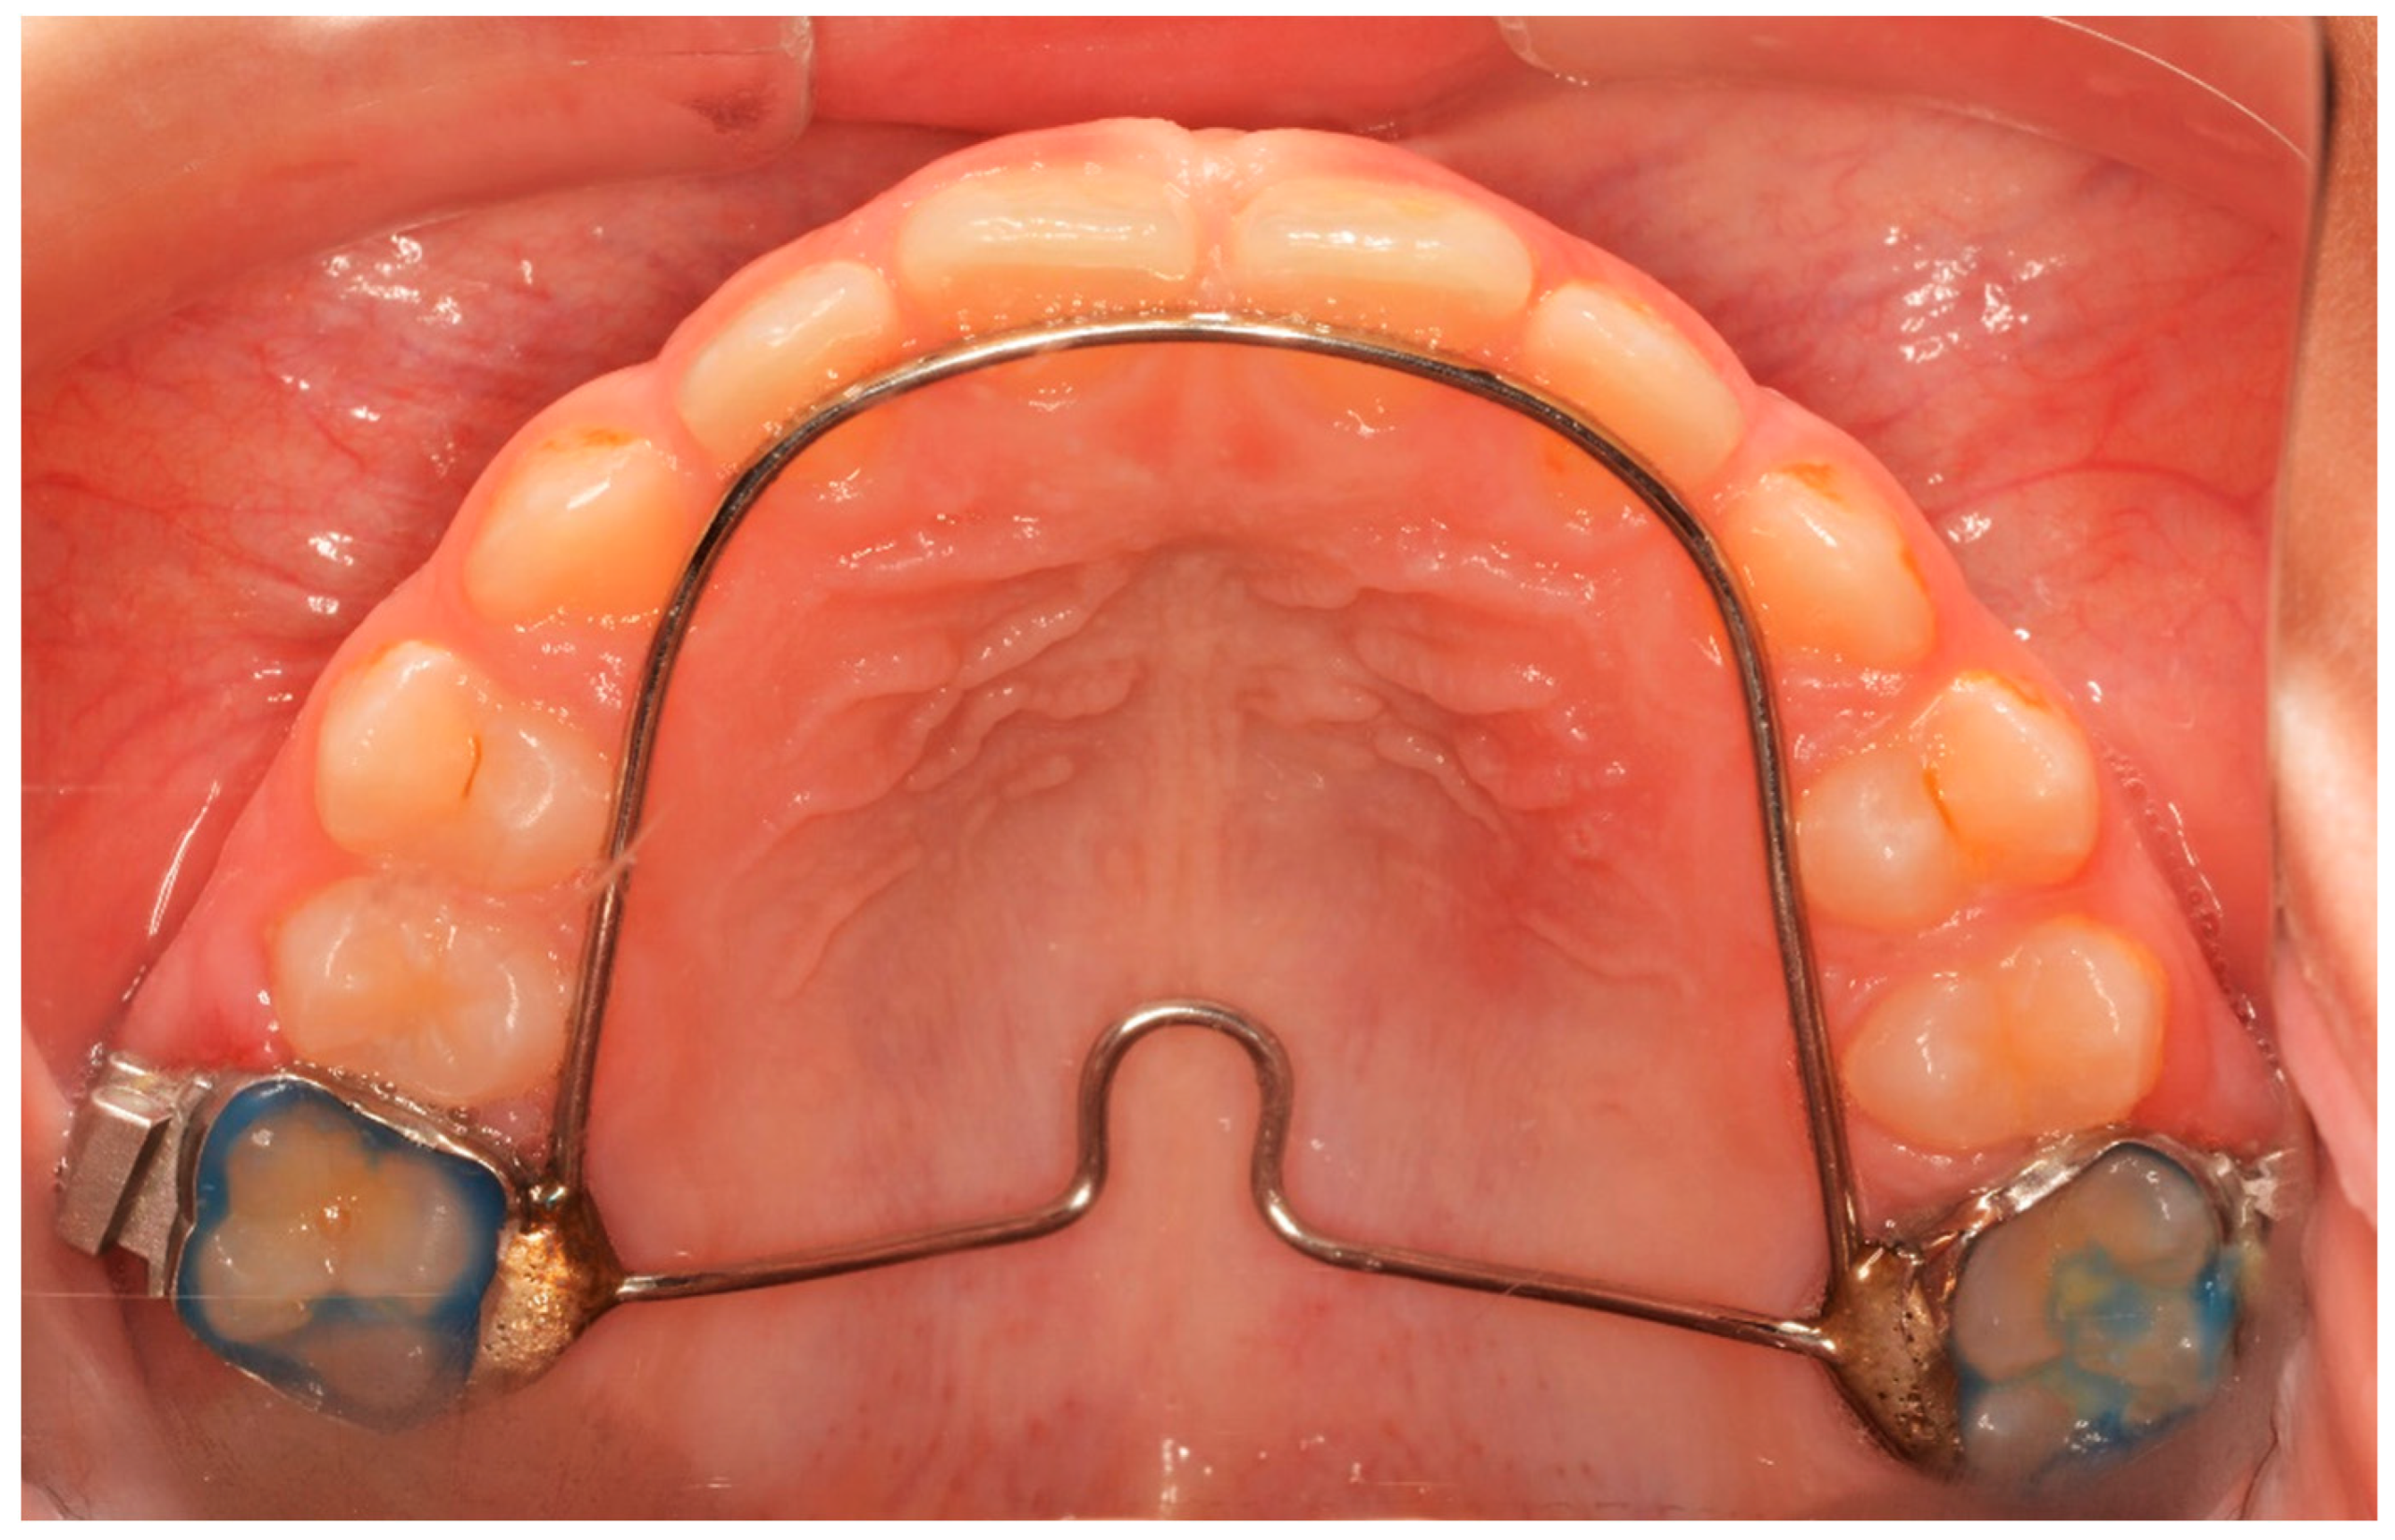

All patients received a Hyrax expander, as the initial part of their treatment, with bands cemented at least on the first maxillary permanent molars and on the first premolars or maxillary deciduous first molars. All Hyrax expanders were manufactured by the same laboratory, and all screws were by the same company. The expansion screw was activated twice a day (0.25 mm per turn, 0.5 mm daily) until the palatal cusp of the maxillary first molar occludes with the buccal cusp of the mandibular first molar. At the end of expansion, the Hyrax screw was stabilized with ligature wire and light-cured composite (Figure 1).

Figure 1.

The end of the active phase of expansion.

The Hyrax screw remained passive during a 6-month retention period after expansion. Until then, neither fixed nor another orthodontic appliance was used. After the passive period, the Hyrax was removed and replaced by a horse-shoe-type transpalatal arch that was used as a retainer, extending to the palatal surface of the incisors (Figure 2). This type of retainer remains in place until all permanent teeth erupt.

Figure 2.

Horse-shoe-type TPA used after T2 time interval.